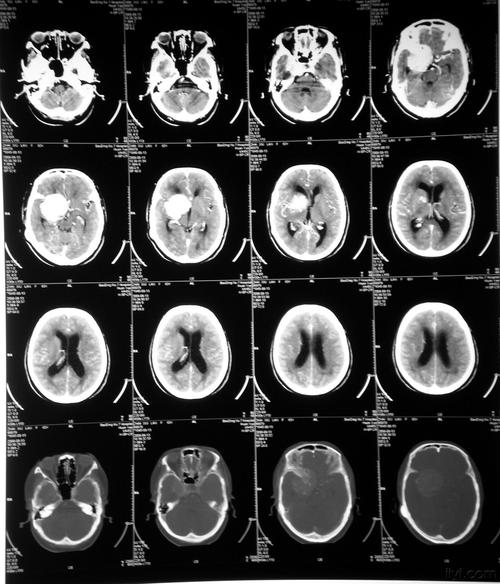

头颅ct检查提示:鞍区可见一类圆形稍高密度影,边界清晰锐利,以宽基底

头颅ct可见鞍区类圆形高密度影

昨天刚收的病人,以头痛就诊,无视神经损害症状,查头颅ct发现鞍区肿瘤

经检查ct:鞍区占位,密度混杂,鞍底骨质破坏,向蝶窦内发展 视力检查